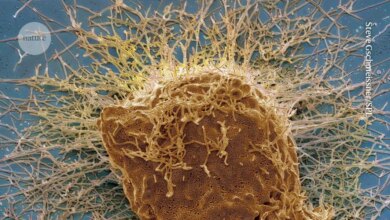

تستكشف الورقة أيضًا الآليات البيولوجية التي يمكن أن تفسر العلاقة بين استخدام الأسيتامينوفين وهذه الاضطرابات. من المعروف أن الأسيتامينوفين يعبر حاجز المشيمة وقد يؤدي إلى الإجهاد التأكسدي ، ويعطل الهرمونات ، ويسبب تغييرات جينية تتداخل مع تطور دماغ الجنين.